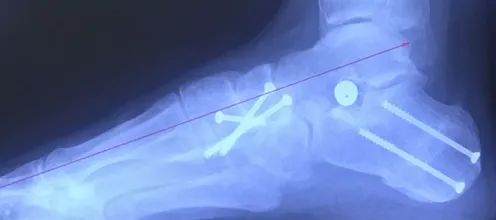

1. In MODERATE TO SEVERE cases a fourth procedure called a “posterior calcaneal osteotomy” is performed.  This procedure is performed through a small incision on the outside of the foot just behind the outer anklebone.  The heel bone is cut in an oblique fashion and slid to the inside of the foot.  It is held in position by two screws.  During the procedure the weightbearing portion of the heel bone is slid ¼” to almost ½” medially.  Weightbearing is reestablished in a more correct position as the heel bone is centered underneath the tibia and the Achilles tendon has a more natural tendency to turn the heel bone under (supinate) rather than turn out (pronate).  The heel bone is a well-vascularized bone that heals more quickly than the Achilles tendon, naviculocuneiform joint fusion or Cotton procedure.  The screws that are placed in the back of the heel under the skin are left in permanently.  We have found that when we are able to get the lower leg to be lined up perfectly straight with the heel bone we get a much better long-term outcome with a much less chance of recurrence of the deformity.